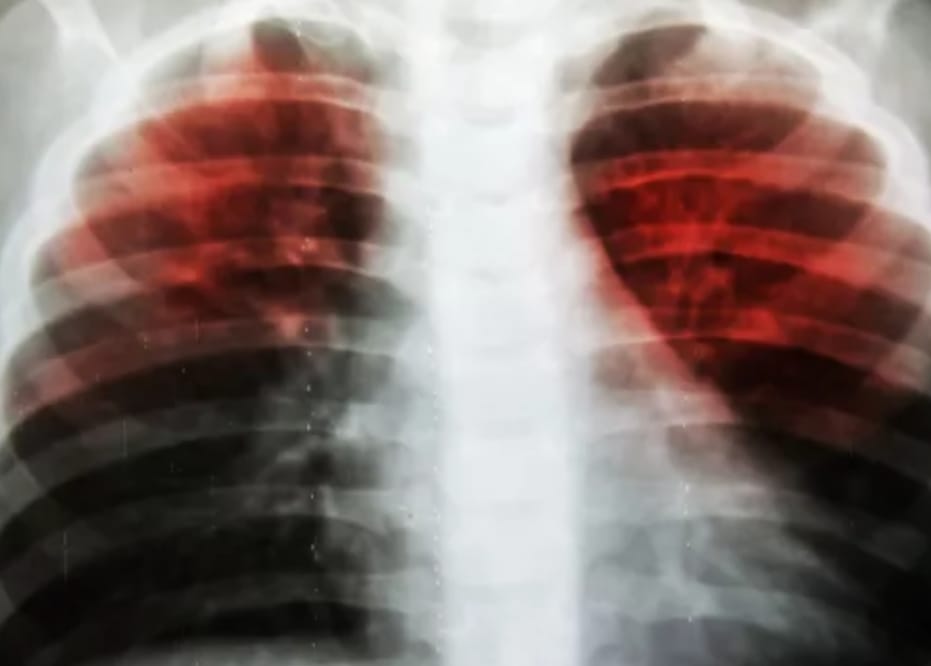

BANGKA SELATAN, TIMELINES.ID — Dinas Kesehatan, Pengendalian Penduduk dan Keluarga Berencana (DKPPKB) Kabupaten Bangka Selatan (Basel), mencatat penderita penyakit Tuberkulosis atau TBC di wilayanya sejak Januari hingga Agustus 2024 mencapai 176 orang.

“Penderita TBC aktif sebanyak 176 orang ini ditemukan di semua kalangan usia yang berisiko tinggi terkena TBC, mulai dari usia anak – anak, remaja hingga dewasa,” kata Kepala DKPPKB Basel, dr. Agus Agus Pranawa, Jumat (8/11/2024) siang.